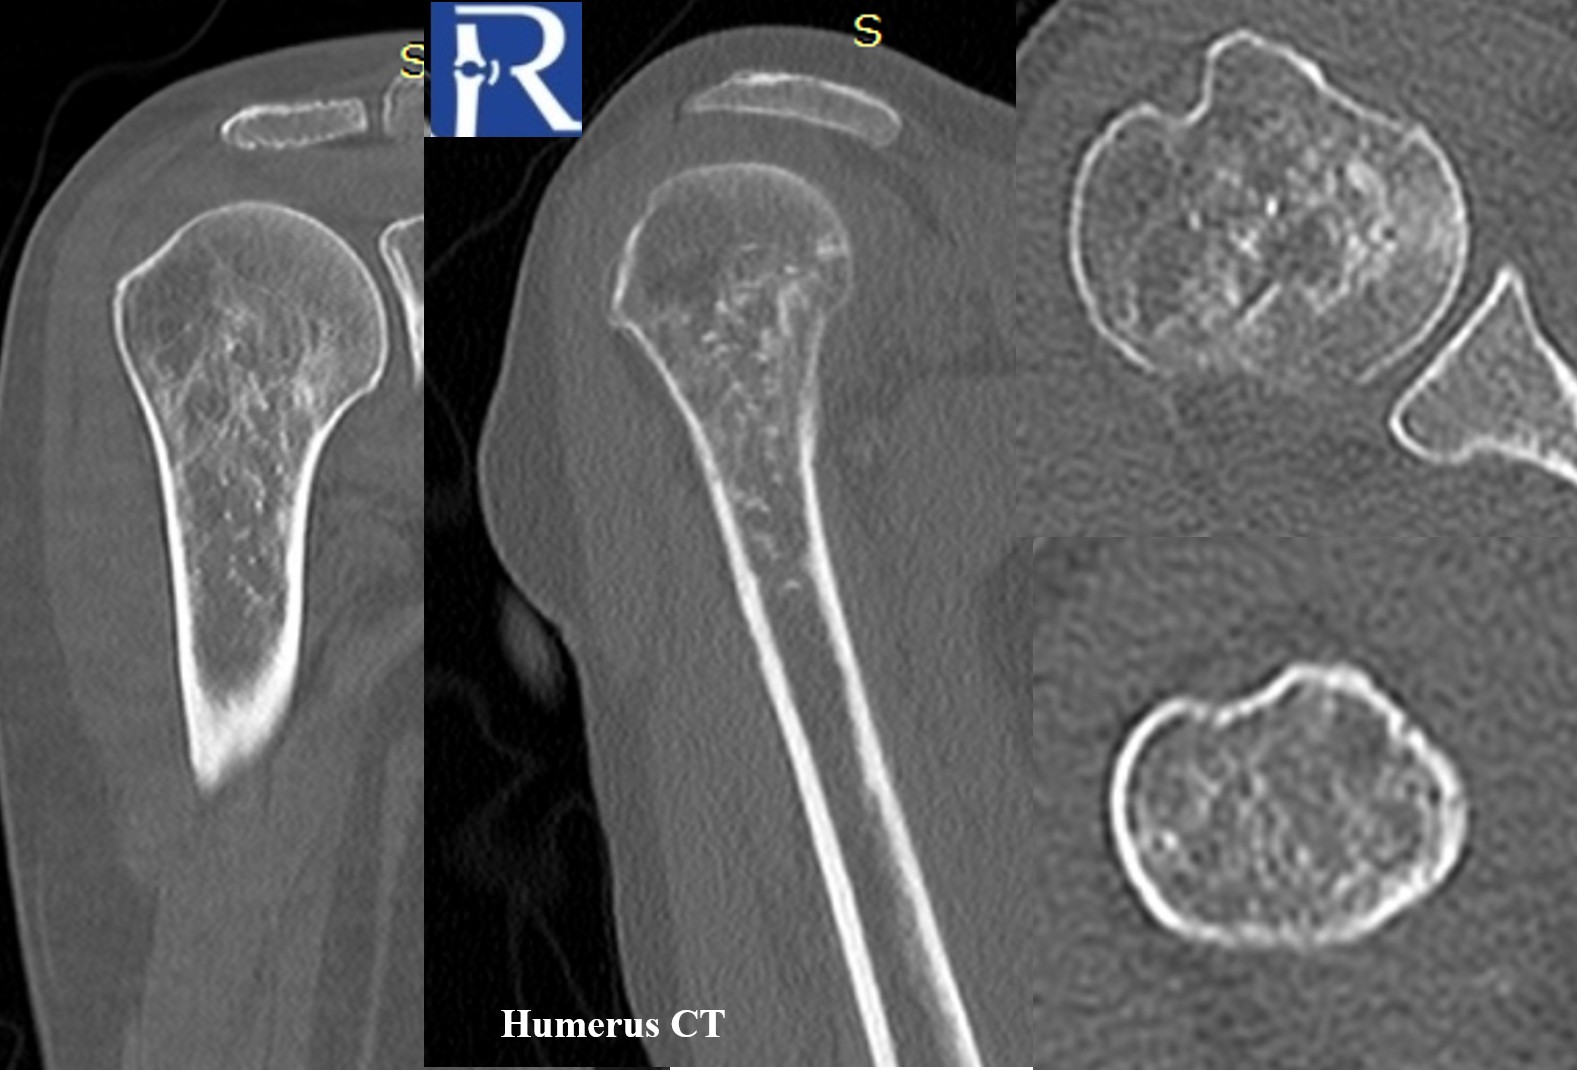

Computed Tomography (CT)

- The lesion is more clearly delineated on CT, showing multiple tiny punctate calcifications embedded within the lesion.

- These punctate densities are suggestive of a chondroid-type matrix, though non-specific.